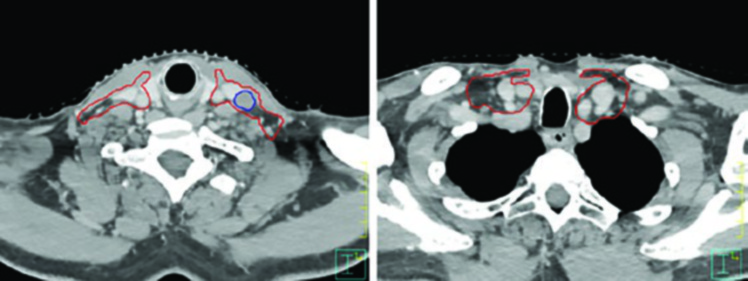

Las figuras de este capítulo ilustran casos reales que ejemplifican los principios de delineación discutidos. El caso de carcinoma amigdalino VPH-negativo cT4N2 demuestra la necesidad de cobertura hasta las láminas pterigoideas e inclusión del nivel IB ipsilateral por invasión de la lengua oral. Observe cómo el GTV (azul) y el CTV (rojo) se adaptan a las barreras anatómicas, respetando hueso y aire mientras se expanden generosamente hacia los tejidos blandos.

El caso de carcinoma amigdalino VPH-positivo cT2N0 tratado unilateralmente muestra cómo, incluso en el escenario de tratamiento ipsilateral, la cobertura se extiende superiormente hasta la lámina pterigoidea ipsilateral. La cobertura ganglionar inicia en la apófisis transversa de C1, abarcando la base de lengua y el paladar blando ipsilaterales sin cruzar la línea media.